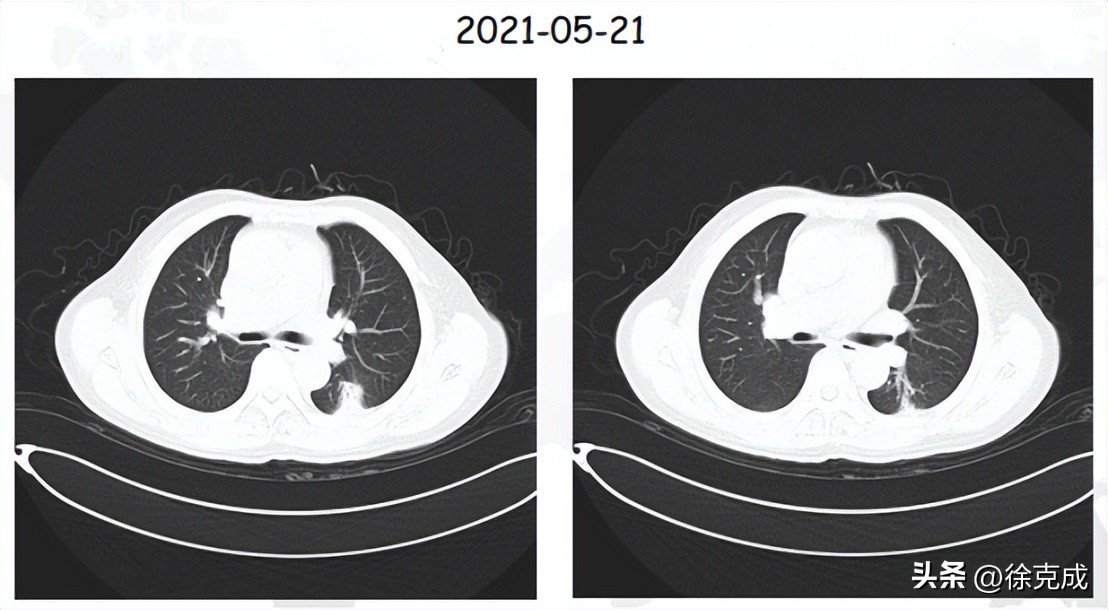

一位66岁的肺部腺癌患者,基础疾病较多,心力衰竭Ⅲ级,一些传统治疗手段无法耐受,为此在院接受冷冻消融治疗。由于患者心功能较差,介入、靶向药等其他方法无法实施,于是他继续在家每天吸氢氧气6L/min,8hr/d,进行康复治疗。目前生存已有3年,病情稳定。